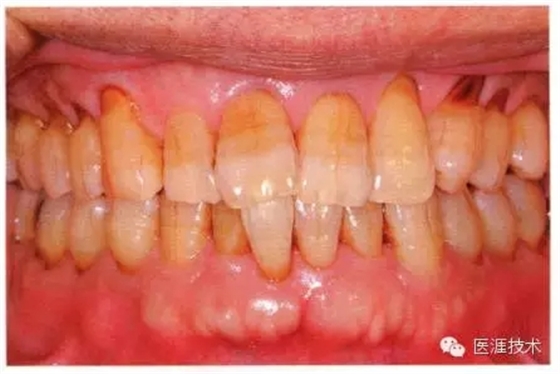

55歲牙周炎男性的臨床照片

55歲男性抽煙患者(1天20支、抽煙35年)。菌斑控制得不好。通過牙周探診,全頜有4~9mm的牙周袋,有1~3度的根分叉部病變。通過X光片觀察,上頜前牙中度牙槽骨吸收,其他地方有中度牙槽骨吸收。受吸煙影響,牙齦纖維性肥厚,呈紅黑色。牙齦幾乎沒有浮腫和發(fā)紅,所以這個病例是從外觀上無法預(yù)測病癥嚴(yán)重程度的病例。